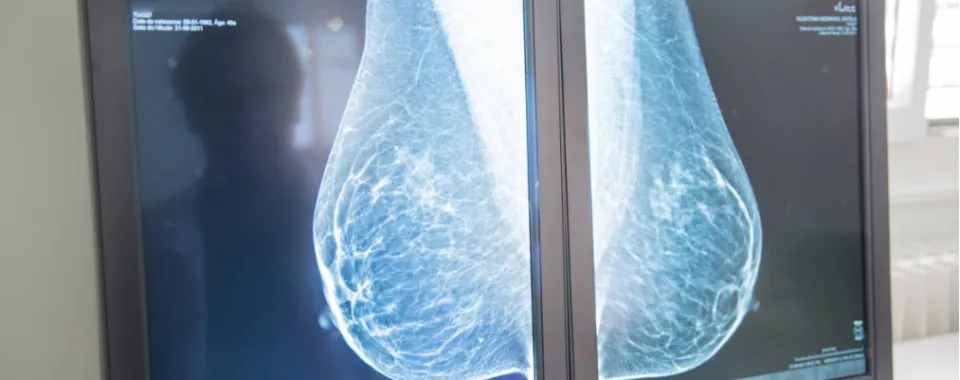

Constitué d’une équipe pluridisciplinaire et d’un plateau technique de dernière génération, le Centre du sein des HUG assure une prise en charge personnalisée et pluridisciplinaire des patients et patientes atteintes d’un cancer du sein. Il est certifié depuis 2014 par la Ligue suisse contre le cancer (LCC) et la Société Suisse de Sénologie (SSS).

Depuis 2016, une collaboration existait déjà entre l’Hôpital de La Tour et les HUG dans le domaine de l’oncologie. Avec ce nouveau partenariat, les deux institutions étendent leur collaboration à l’ensemble de la prise en charge du cancer du sein c’est-à-dire en matière de diagnostic, de traitements chirurgicaux, radio-oncologiques et oncologiques, de reconstruction mammaire et de suivi.